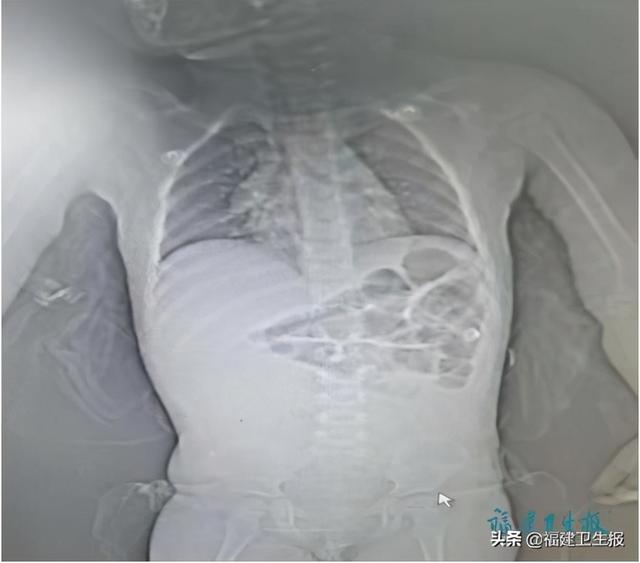

文章插图

黄怃主任医师当即作出指导 , 患儿病情危重 , 必须立即急诊开腹探查 。 经术中诊断 , 轩轩绞窄性肠梗阻(小肠坏死)、急性弥漫性腹膜炎、感染性休克;术后转入该院儿科重症监护室(PICU) 。